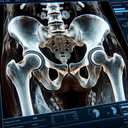

МРТ кульшових суглобів

МРТ кульшових суглобів – це неінвазивний метод діагностики, який використовує магнітне поле та радіохвилі для отримання детальних зображень. Це дослідження допомагає лікарям виявити патології, такі як артрит, травми, запальні процеси або новоутворення. Якщо ви шукаєте надійний медичний центр у Хмельницькому, зверніть увагу на "Ультрадіагностику"...